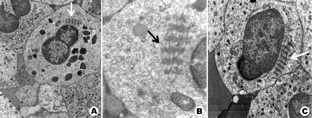

患者,女,25岁,主因发现血小板减少2年,月经增多3个月,牙龈出血10 d,为进一步治疗入住本院。体检:体温36.6 ℃,脉搏80次/min,呼吸20次/min,血压115/82 mmHg(1 mmHg=0.133 kPa)。全身皮肤黏膜无黄染、无出血点,少量陈旧性瘀斑;浅表淋巴结未触及;咽无充血,扁桃体不大;胸骨无压痛,双肺呼吸音清,未闻及干、湿罗音,无胸膜摩擦音。肺CT、头颅CT未见异常。心率80次/min,律齐,心音有力,各瓣膜听诊区未闻及杂音,无心包摩擦音。腹平软,肝脾肋下未触及。既往5年前患胃溃疡(胃镜证实),否认2型糖尿病、高血压病史,无肾脏损害、听力障碍及白内障。患者有一位亲属发现血小板减低。实验室检查:血常规:Hb 147 g/L,Ret 60.7×109/L,WBC 5.49×109/L,PLT 27×109/L。外周血涂片未见幼稚细胞,部分成熟粒细胞胞质内可见大小不一的蓝斑,巨大血小板易见(图1)。骨髓象:有核细胞增生活跃。粒系各期均见,以中晚幼细胞为主,部分成熟粒细胞胞质内可见一个或多个圆形或不规则形淡蓝色包涵体,可见巨大血小板(图2)。电子显微镜检查:结果可见粒细胞内包涵体呈横行分布的核蛋白体,并有纵向微丝相连(图3)。免疫分型:流式细胞术检查以CD45细胞侧向角散射光强度(SSC)设门,CD3+细胞占淋巴细胞比例:76.5%,CD3+CD4+占淋巴细胞比例:33.0%,CD3+CD8+占淋巴细胞比例:40.3%,CD3+CD4+/CD3+CD8+:0.82。血小板聚集率:ADP诱导率:65.9%,胶原诱导率:66.7%。血块收缩试验:24 h不收缩。凝血常规及肾功能检查均正常。基因测序:应用美国ABI公司的3730XL测序仪对先证者非肌性肌球蛋白重链9(nonmuscle myosin heavy chain 9,MYH9)基因1、10、16、25、26、30、31、38、40号外显子PCR扩增产物进行测序[1,2,3,4],确认突变位点在22号染色体36691607位置(MYH9基因26号外显子的3429处),命名为c.3429 T>G,该突变使相应密码子由GCU变为GCG,命名为p.A1143A,为同义突变(图4)。家系调查显示患者有一位亲属患有血小板减少症,其余无异常(图5)。